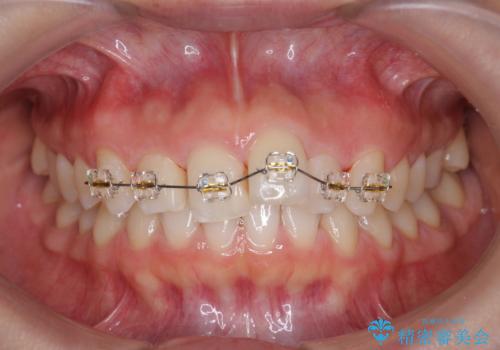

出っ歯に見える前歯の改善 部分ワイヤーとマウスピース矯正

- インビザライン +部分ワイヤー矯正

- 出っ歯に見える前歯の改善を希望され、来院されました。

マウスピースでは改善の難しい歯の動きを部分ワイヤー矯正で整えたのち、奥歯の噛み合わせや細かい歯の並びをマウスピース矯正インビザラインで整えていきます。